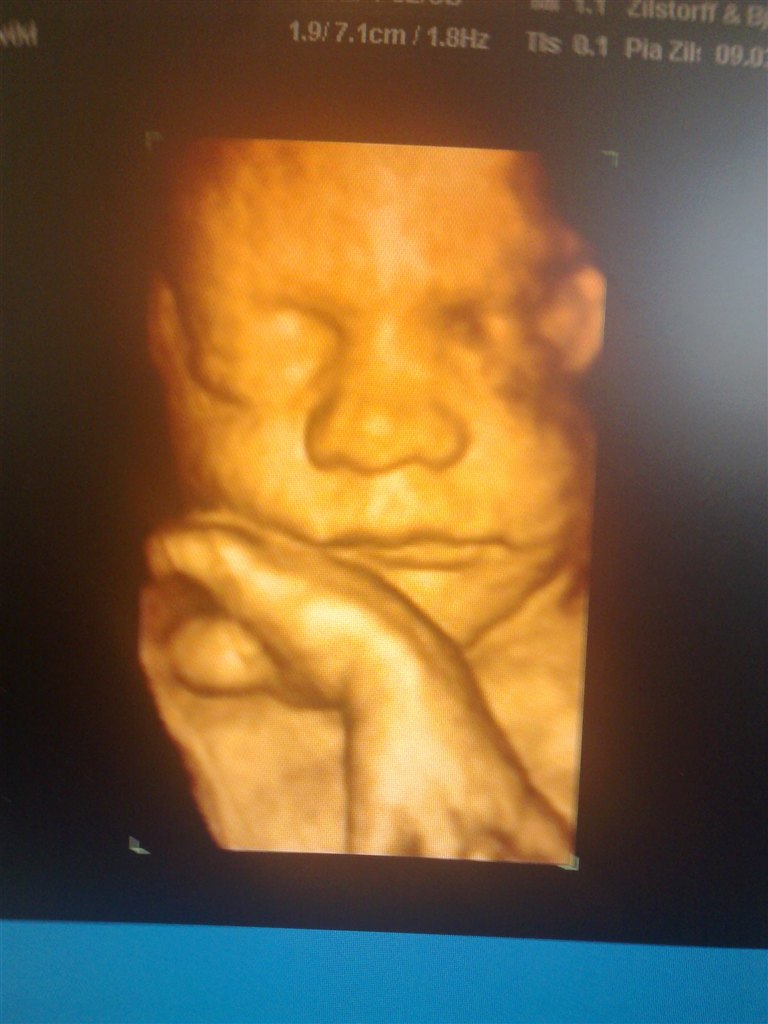

Her er det min lille dreng  Han ville selvfølgelig ikk vise hele sit ansigt så har kun fået "noget" af det

Hihi men fik faktisk også et billede af hans dutti, så nu er vi 100% sikker på at det er en dreng  haha.. Så har vi det først billede til hans konfirmation

Vedhæftede fotos (klik for at se i fuld størrelse)